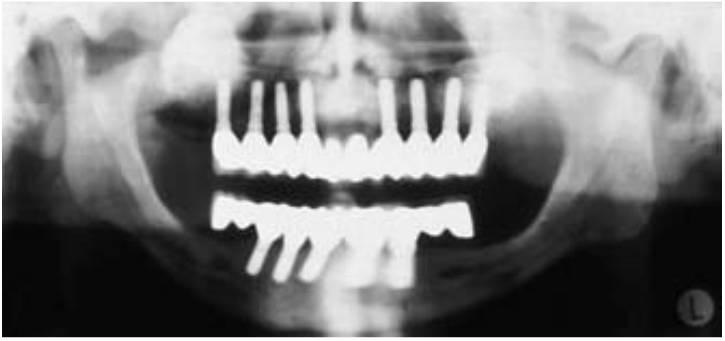

La mayoría de las fuerzas aplicadas sobre el cuerpo de los implantes osteointegrados se concentran sobre la cresta, de 7 a 9 mm, de hueso, independientemente del diseño del implante y de la densidad ósea. Por ello, la altura del cuerpo del implante no es un método efectivo para valorar los efectos de la altura coronaria. En otras palabras, la proporción corona-raíz es un concepto prostodóncico que puede guiar al dentista restaurador para evaluar el pilar de un diente natural. Cuanto mayor sea la raíz del diente natural, menor será la longitud de la altura coronaria, que actúa como palanca de rotación del diente alrededor de un eje situado en los dos tercios inferiores de la raíz. Sin embargo, la proporción altura coronaria-implante no presenta una proporción directa. La altura coronaria es un voladizo vertical que magnifica cualquier fuerza lateral o de voladizo en cualquier restauración dental o implanto-soportada. Sin embargo, esta situación no se mejora aumentando la longitud del implante para disminuir el estrés. El implante no rota alejándose de la fuerza en función de su longitud. En vez de esto, captura la fuerza en la zona de la cresta. Cuanto mayor sea el EAO, normalmente se necesita aumentar el número de implantes requeridos para la prótesis, especialmente en presencia de otros factores de fuerza. Esto supone un cambio paradigmático completo de los conceptos aceptados originalmente, con muchos implantes en un hueso disponible más abundante y coronas de pequeña altura y menores implantes con alturas coronarias mayores en un hueso atrofiado (figs. 6-26 y 6-27).